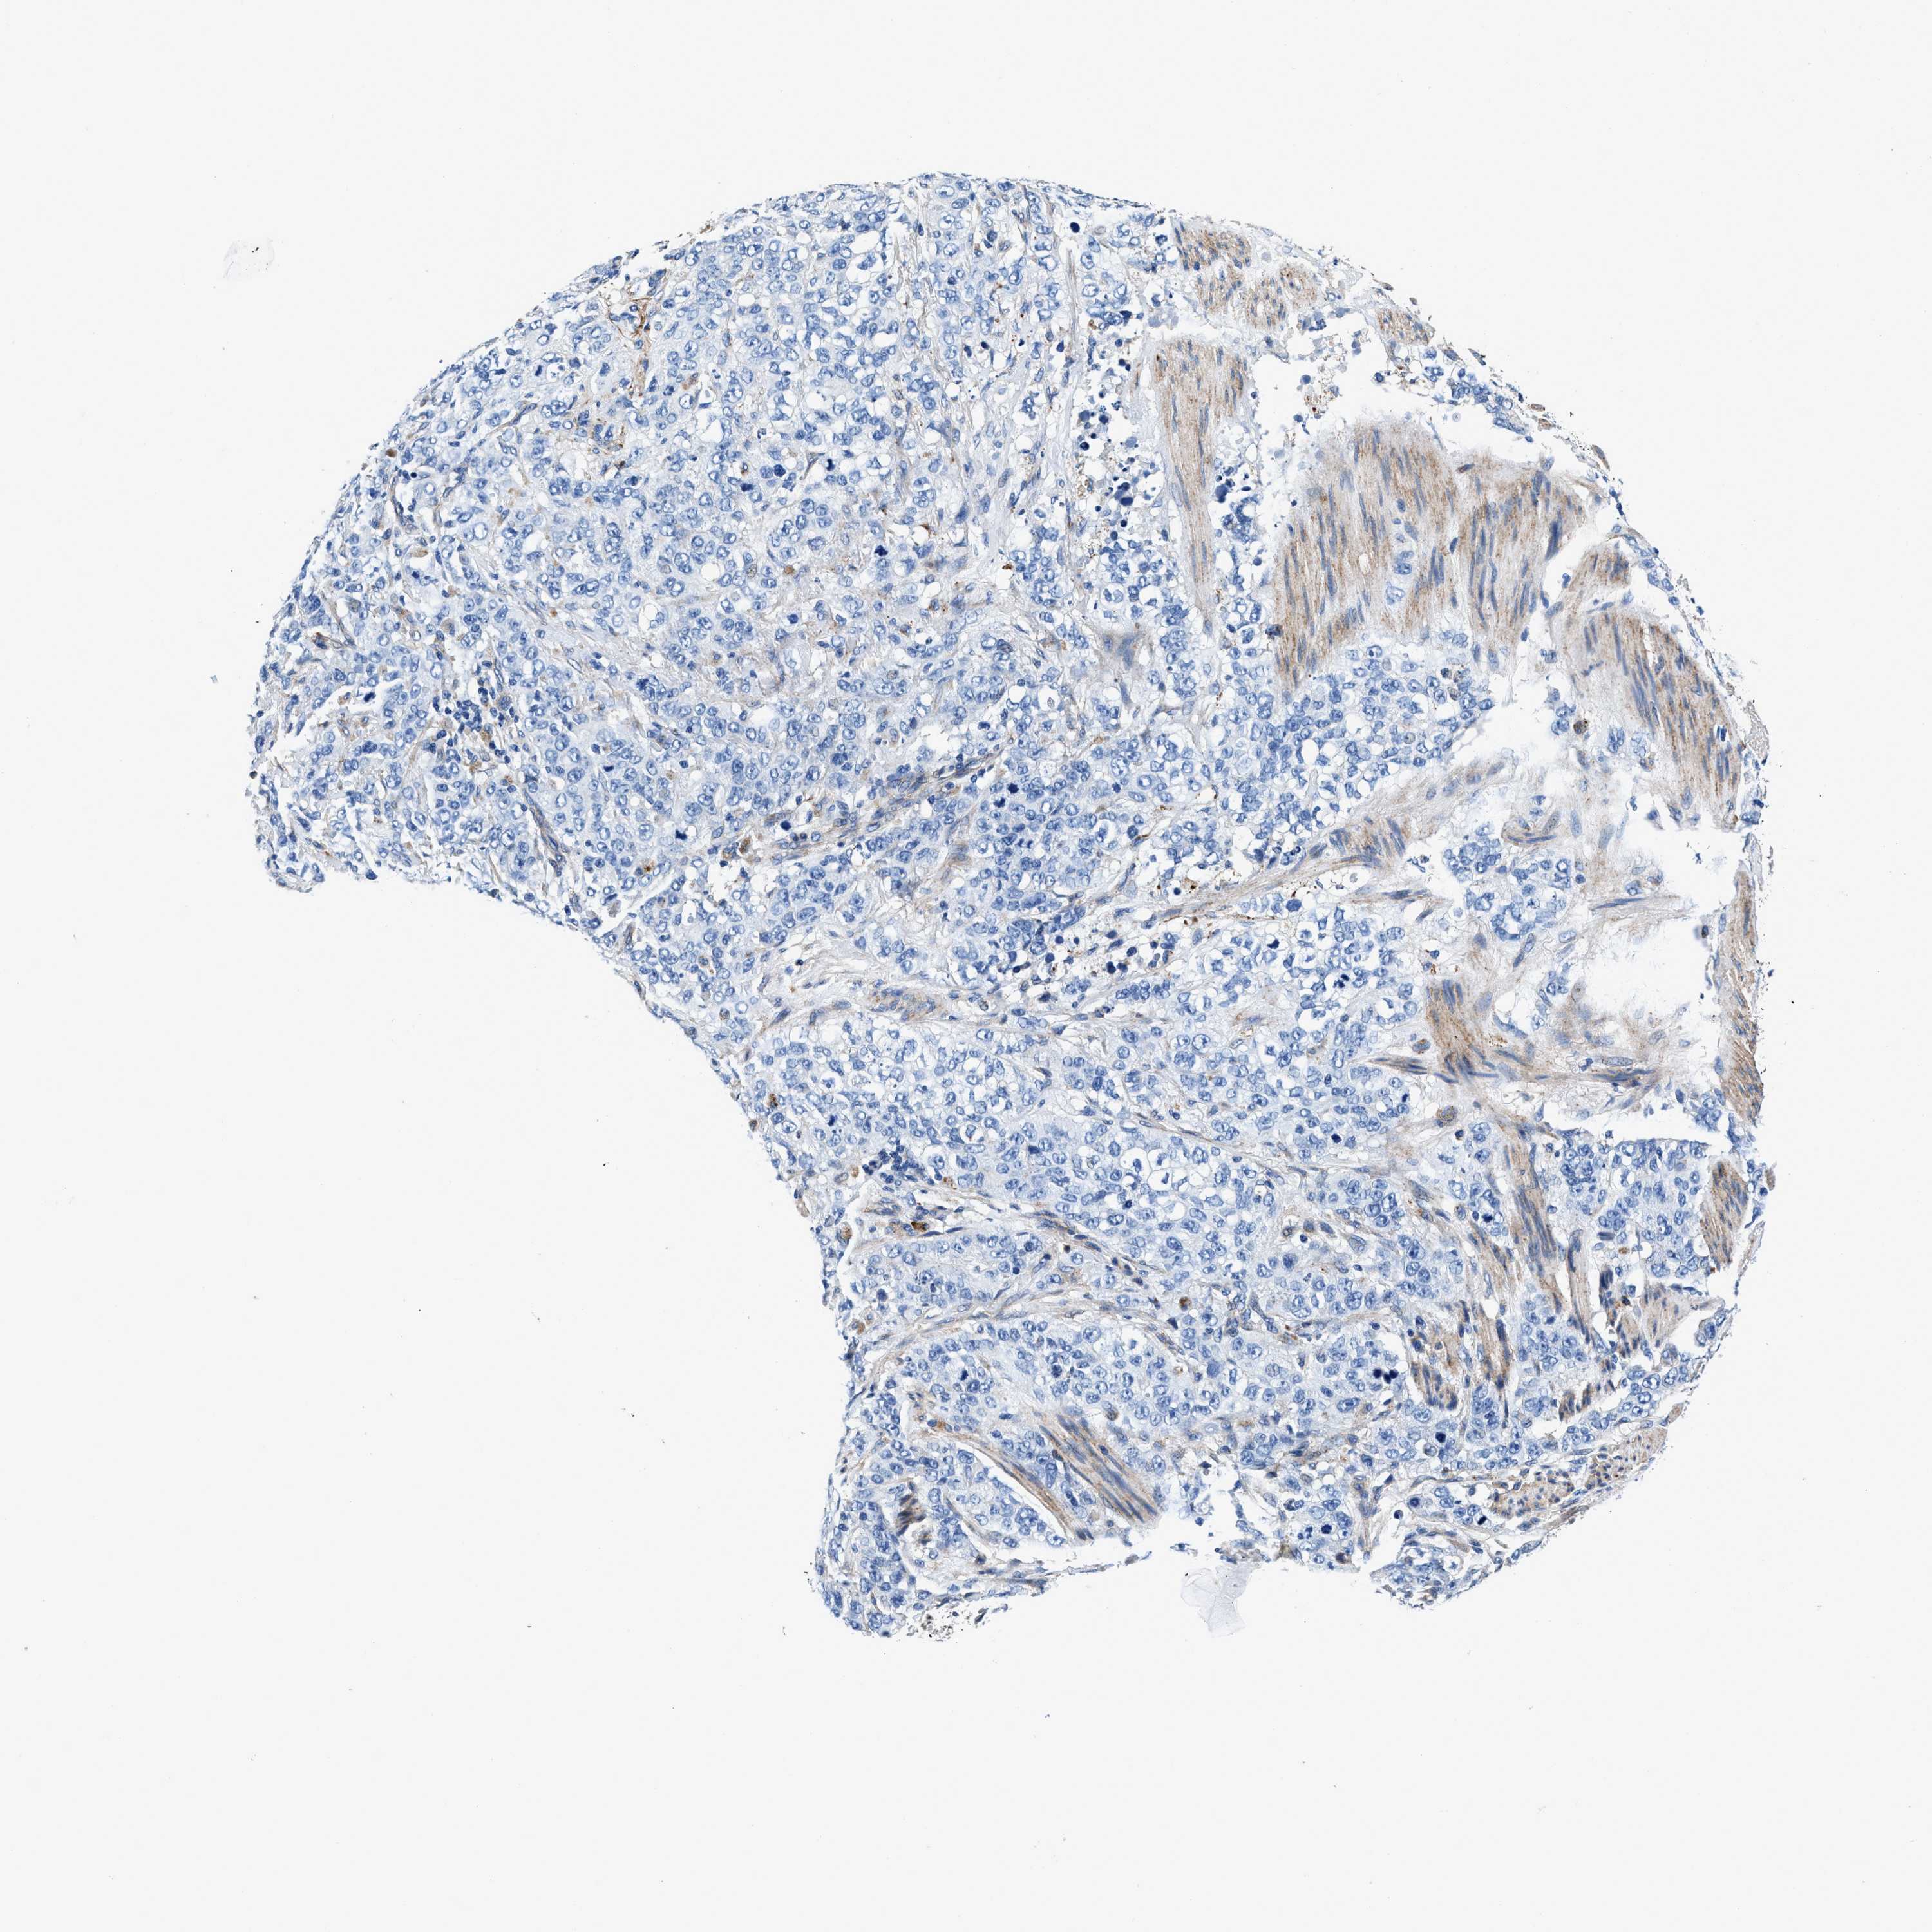

STOMACH CANCER - Protein expressioni

A mouse-over function shows sample information and annotation data. Click on an image to view it in a full screen mode. Samples can be filtered based on level of antibody staining by selecting one or several of the following categories: high, medium, low and not detected. The assay and annotation is described here.

Note that samples used for immunohistochemistry by the Human Protein Atlas do not correspond to samples in the TCGA dataset.

Antibody stainingi

Antibody staining in the annotated cell types in the current human tissue is reported as not detected, low, medium, or high, based on conventional immunohistochemistry profiling in selected tissues. This score is based on the combination of the staining intensity and fraction of stained cells.

Each image is clickable and will lead to virtual microscopy that enables deeper exploration of all samples and also displays staining intensity scores, fraction scores and subcellular localization as well as patient and tissue information for each sample.

Antibody CAB001960

Antibody CAB016353

Staining

High

Medium

Low

Not detected

Intensity

Strong

Moderate

Weak

Negative

Quantity

>75%

75%-25%

<25%

None

Location

Nuclear

Cytoplasmic/membranous

Cytoplasmic/membranous,nuclear

Adenocarcinoma, NOS

Adenocarcinoma, High grade